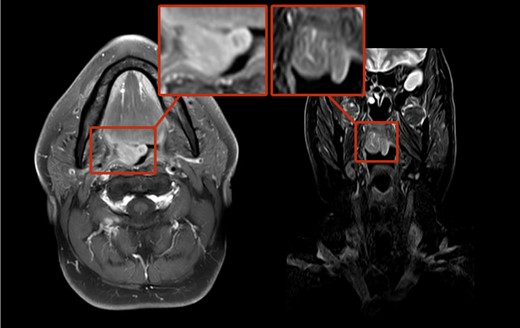

A 65-year-old male was referred to our department with a constant urge to clear the throat for a time span of 12 months. In addition, the patient stated his progressing inability to swallow food. Due to these symptoms, a resection of the thyroid gland had been carried out earlier showing struma colloides nodosae as well as bilateral parathyroidal adult rhabdomyomae. Even so, there was no relief in symptoms. At outpatient presentation at his dentist, a slight swelling of the soft palate was felt and the patient was referred for further therapy. Endoscopic examination as well as magnetic resonance imaging (MRI; Fig. 1) unveiled a tumor on the right side of the soft palate with a size of 5 × 5 cm2 and distinct demarcation to the surrounding tissue. Subsequently, the lesion was completely excised (Fig. 2) and histopathological analysis was conducted that showed a circumscribed but not encapsulated mesenchymal tumor with polygonal cell formation. The cells presented a granular cross-striated eosinophilic cytoplasm, large round vesicular nuclei and so called spiderweb cells (Fig. 3). Immunohistochemically, the cytoplasm of the cells was 100% positive for antibodies to desmin and S100 (Fig. 4). Additional immunohistochemical markers showed slight nuclear positivity for myogenin and nuclear negativity for AE1/3, CD68 as well as melan A. The histological examination confirmed ARM without signs of malignancy. At a total follow-up of 3 years, including MRI scan, no signs of recurrence were detected.

Hematoxylin-eosin (H&E) staining: polygonal cell formation with granular cross-striated eosinophil cytoplasm and large round vesicular nulei are seen.